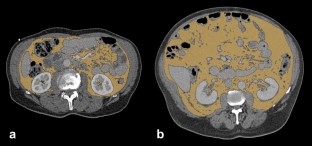

In this retrospective study, two groups were included: nccRCC group and control group. Total adipose tissue (TAT) area, VAT area and subcutaneous adipose tissue (SAT) area were measured in both groups. VAT/SAT ratio was subsequently calculated.

Fig. 1

Fig. 2